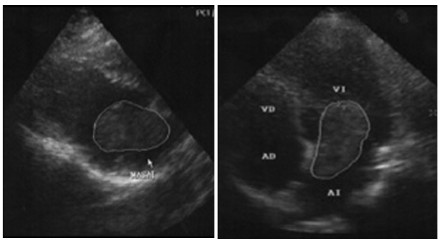

Mediante ecografía transtorácica se evidenció imagen heterogénea, hiperecoica, ovoidea adherida al septum interauricular que prolapsa en diástole al ventrículo izquierdo, de 4,52 × 2,25 cm (Figura 1 A).

Posteriormente, se realiza exéresis tumoral completa cuya anatomía patológica confirmó la presencia de neoplasia mixoide con disgregación hemorrágica compatible con MC (Figura 1 B).